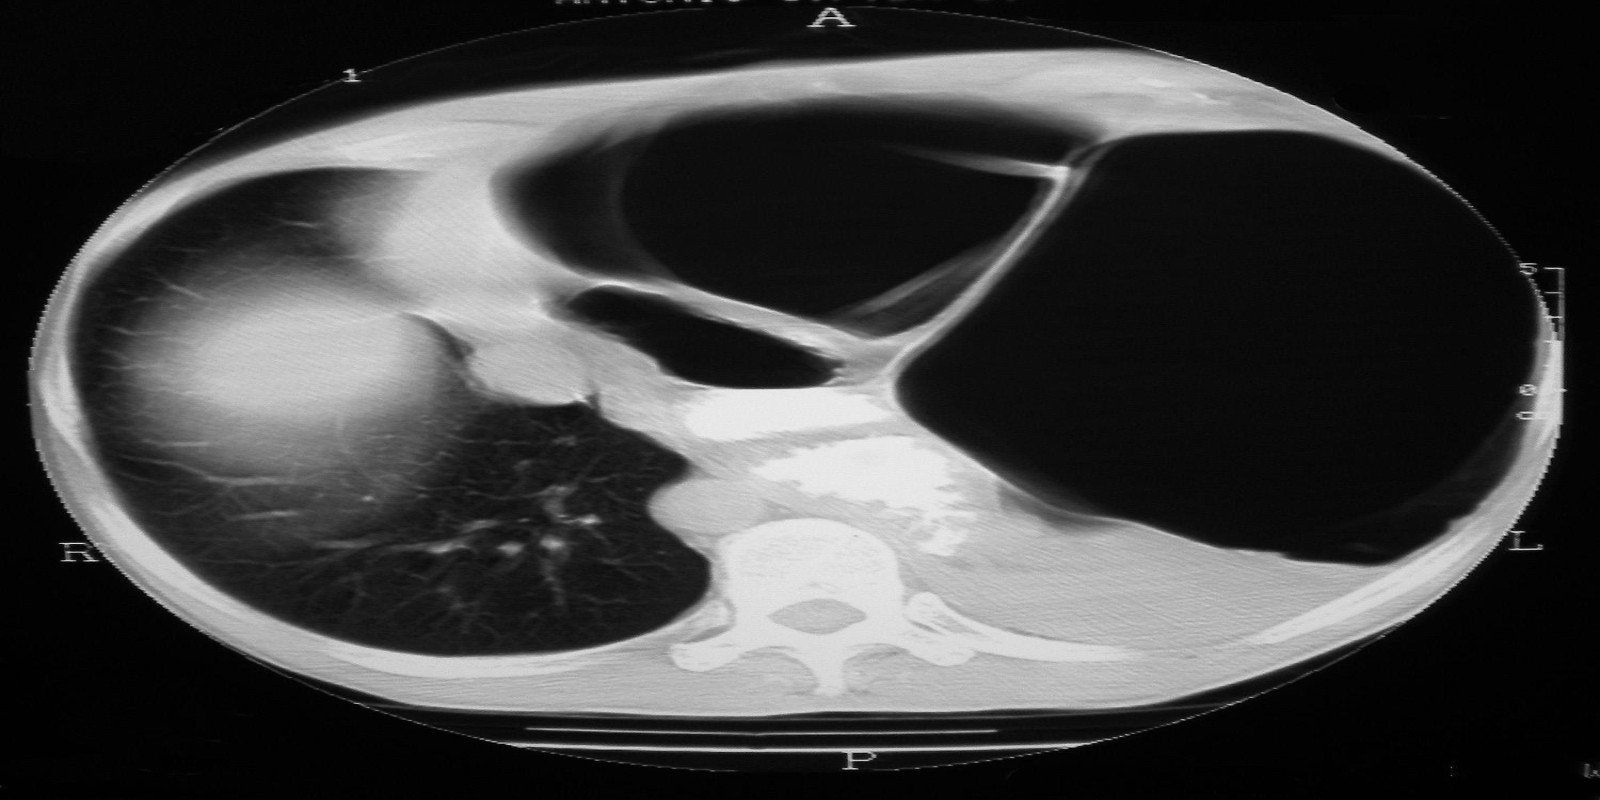

Eventração diafragmática

Diaphragmatic Eventration